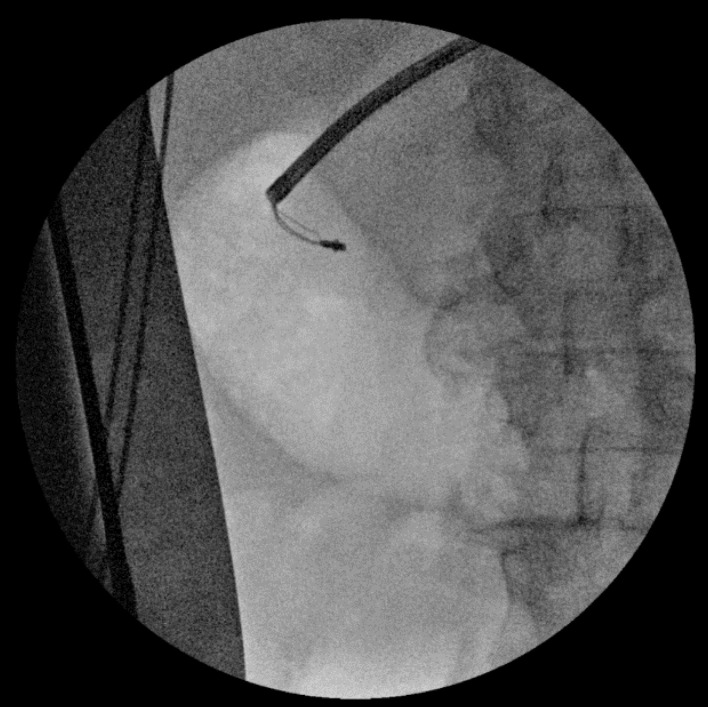

Endoscopic retrograde cholangiopancreatography (ERCP) is an important technique for treating biliary obstruction. A case report of a 75-year-old male with diagnosed choledocholithiasis and cholangitis was presented. He had a history of hepatic surgery 45 years ago, and during the ERCP, an unusual clinical scenario was encountered. Retained extraction basket during ERCP is a rare but known complication and there are no standard recommendations to manage it. To our knowledge, this is the first case report described in the literature with retention of an extraction basket in surgical sutures at ERCP and the longest period from surgery to stone formation in the biliary system. This case report aims to emphasize that in patients with a history of hepatobiliary surgery, postoperative material can cause complications during ERCP.